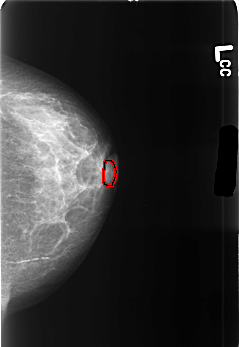

B_3445_1.LEFT_CC

LEFT_CC LINES 4504 PIXELS_PER_LINE 3104 BITS_PER_PIXEL 12 RESOLUTION 50 OVERLAY

FILE: B_3445_1.LEFT_CC.OVERLAY

TOTAL_ABNORMALITIES 1

ABNORMALITY 1

LESION_TYPE MASS SHAPE LYMPH_NODE MARGINS N/A

ASSESSMENT 2

SUBTLETY 3

PATHOLOGY BENIGN_WITHOUT_CALLBACK

TOTAL_OUTLINES 1

BOUNDARY